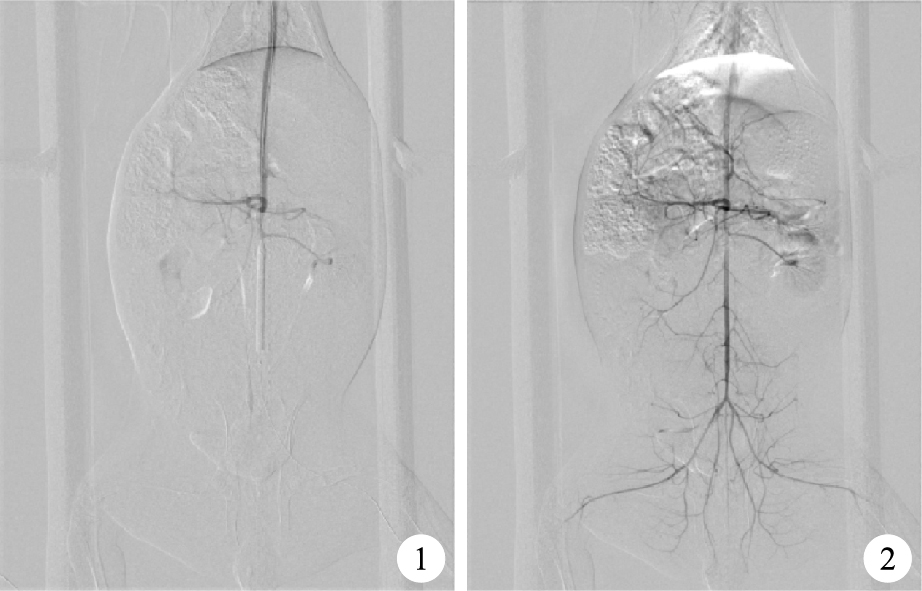

實驗前兔禁食12 h,自由飲水。腹腔注射戊巴比妥30 mg/kg麻醉,麻醉滿意后從左側頸動脈引入4 F球囊至腎下主動脈,阻斷血管,制成雙后肢缺血模型(圖 1)。阻斷血管90 min后,經球囊控制性灌注血必凈30 min后撤出球囊,使后肢血運恢復(圖 2),制成雙后肢缺血再灌注損傷模型。缺血時間共2 h,再灌注時間為4 h。血必凈灌注組控制性灌注方法:首先將血必凈按每公斤體質量抽取4 mL注射液,用生理鹽水配至10 mL,使用注射泵持續30 min泵入。鹽水對照組則使用相同方法造模,同樣使用控制性灌注的方法,灌注液為生理鹽水(4 mL/kg)。假手術組僅成功完成頸動脈穿刺,不進行后面的操作,即不予缺血及再灌注處理。